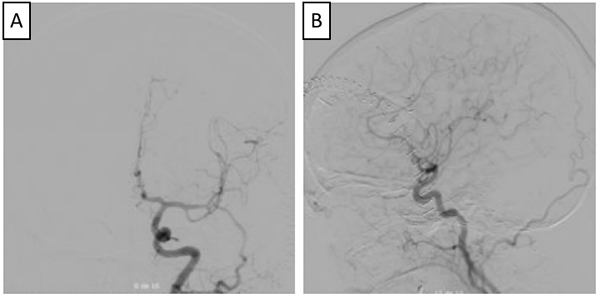

Paciente de género femenino, de 51 años de edad, que consultó a oftalmología por un cuadro clínico de 20 días de evolución consistente en disminución súbita de la agudeza visual del ojo derecho, no asociado a dolor, síntomas sistémicos, ni compromiso de los movimientos oculares. En la evaluación  inicial se encontró en el ojo derecho un defecto pupilar aferente, agudeza visual mejor corregida de 20/400, discromatopsia con test de Ishihara 0/14,  y excavación del 20% en el borde del disco óptico, compatibles con neuritis óptica retrobulbar. En la campimetría por confrontación, se encontró una hemianopsia temporal derecha. A su ingreso a urgencias se le realizó tomografía de cráneo en la que se encontró lesión selar y supraselar, por lo cual se solicitó RMN cerebral contrastada bajo la sospecha de un macroadenoma hipofisiario. En la RMN (Ver Imagen 1) se identificó lesión ovalada, de localización supraselar, con efecto de masa sobre el quiasma óptico y la porción cisternal de ambos nervios ópticos, principalmente del lado derecho, con cambios en secuencias de susceptibilidad, compatible con aneurisma de la AComA parcialmente trombosado.

Figura 1

. RMN de cráneo en la que se identifica lesión sacular de localización supraselar con efecto de masa, mide 22 mm x 19 mm x 17 mm (A), desplaza y comprime el quiasma óptico y la porción cisternal de ambos nervios ópticos, especialmente el del lado derecho (B), tiene un área en forma de media luna que realza tras la administración del medio de contraste (B y C). En la parte inferior se observa la Arteriografía cerebral con un aneurisma sacular de contornos irregulares, localizado en el segmento comunicante anterior de 8mm x 6mm x 5 mm (D, E y F).

Para definir con mayor detalle la anatomía vascular, se realizó una arteriografía (Ver Imagen 1), con la que se confirmó la presencia de un aneurisma sacular de la arteria comunicante anterior, de contornos irregulares, de 8x6x5 mm, sin signos de ruptura con una orientación antero-inferior. Esta clara diferencia entre el tamaño de la lesión en la RNM y la arteriografía confirma la presencia de un trombo intra-aneurismal.

Figura 3

. Arteriografía de control postoperatoria (A y B), en la que se observa adecuada exclusión de aneurisma cerebral